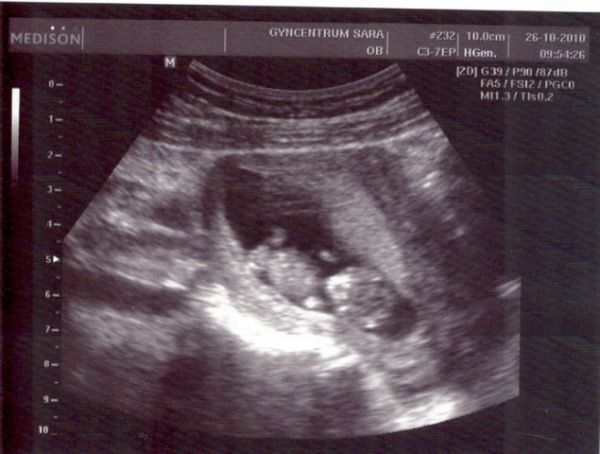

zítra mě čeká další UZ v 9. týdnu, mám za sebou UZ s potvrzením těhotenství (těh. váčku), pak v 6. tydnu potvrzení srdeční činnosti. Tak se těším na zítřek, že zase uvidím ten svůj poklad a doufám, že bude vše ok. Na mimi jsme čekali delší dobu, ale nakonec nám v centru pro IVF hodně pomohli a otěhotněla jsem i bez umělého oplodnění ;) Hrozně se těším, jak v květnu už budu mít u sebe toho broučínka ...Všem vám přeji jen to dobré a hodně radosti se svých očekávaných pokladů. krásný den a opatrujte se Jana